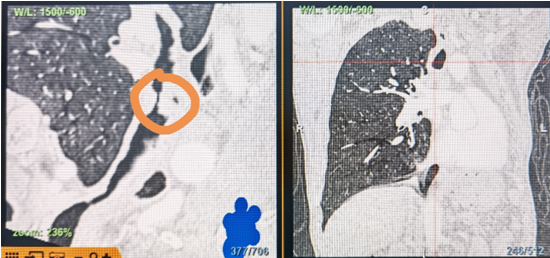

時間就是生命!了解患者病情后,歐陽海峰立刻啟動氣道梗阻緊急救治通道,協(xié)調(diào)院前轉(zhuǎn)運,急診快速入院流程。凌晨患者入院胸部CT顯示,現(xiàn)存唯一的呼吸通道在右主支氣管處,狹窄處僅約3毫米,患者命懸一線!

運用呼吸介入技術(shù),軟硬鏡結(jié)合快速開通氣道,是患者目前唯一可行的治療方案,手術(shù)刻不容緩!但存在麻醉后氣道完全塌陷閉合、大出血、窒息等巨大風險?;颊叽饲敖舆B轉(zhuǎn)診3家醫(yī)院,均建議保守支持治療或轉(zhuǎn)院。歐陽海峰詳細了解患者病史,全面評估影像檢查結(jié)果后,決定盡快進行手術(shù),組織醫(yī)護團隊對患者進行持續(xù)密切監(jiān)測,充分保障其術(shù)前安全。